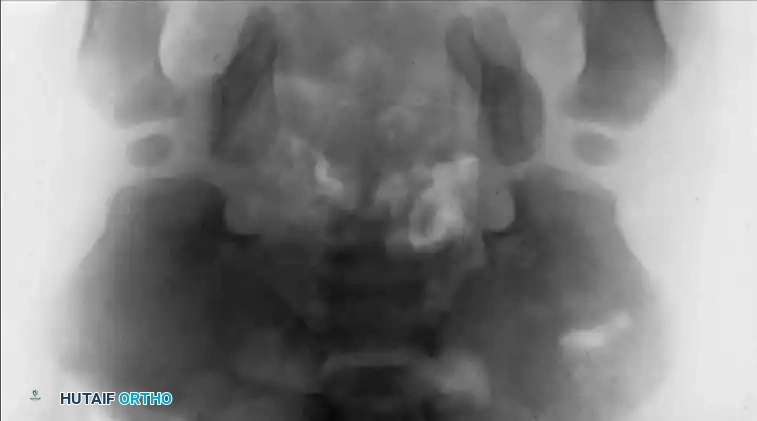

Fig. 27-37 B: Preoperative anteroposterior radiograph of a 1-year-old child demonstrating severe pubic diastasis and lateral flare of the iliac wings.